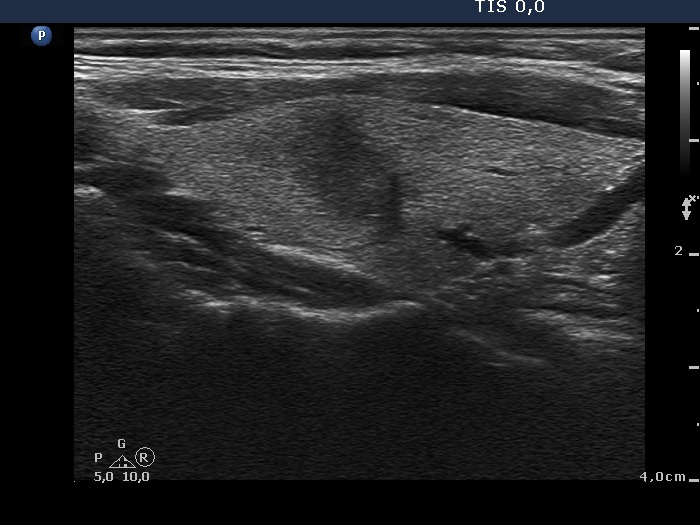

Follow-up 2 months after the first visit (3rd row of images):

Clinical presentation: Within 24 hours of the administration of 32 mg methylprednisolone, the neck complaints and subfebrility had stopped. When the patient reduced the dose to 8 mg daily for 2 weeks as suggested, the left lobe became sensitive. This tenderness has now been significantly reduced, but still persisted at times.

Palpation: The left lobe was tender on palpation.

Laboratory tests: TSH 1.62 mIU/L, FT4 9.97 pM/L, CRP 0.1 mg/L.

Ultrasonography: The right lobe decreased in size as did the extent of hypoechogenic areas in this lobe. The left lobe remained unchanged.

Suggestion: Discontinuation of steroid therapy. TSH in three months.